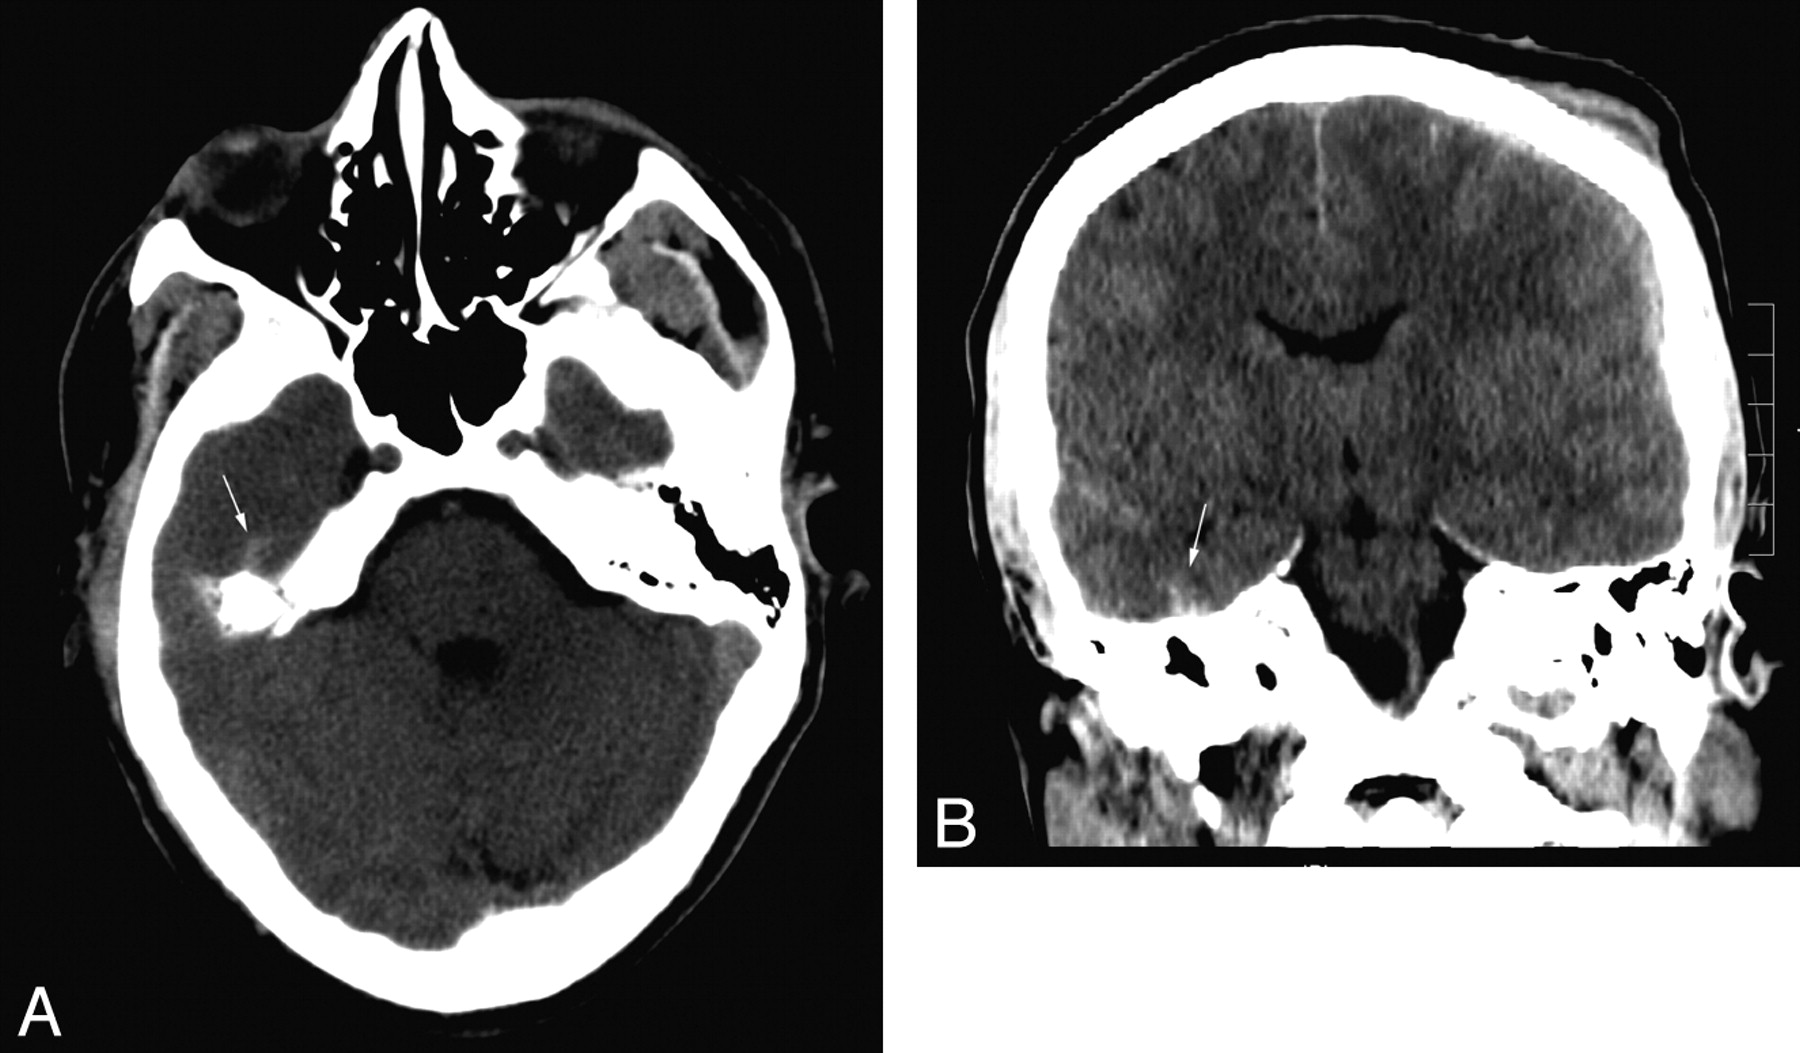

In our study, the 2 most common locations for a false-negative finding on axial images were the floor of the anterior cranial fossa (n = 6) and the floor of the middle cranial fossa (n = 3), a total of 9/15 (60%) of the false-negatives from the independent axial review. Figures 1 and 2 demonstrate small hemorrhagic contusions along the floor of the right anterior and middle cranial fossas. On the axial series, these are partially obscured by volume averaging from the immediately adjacent bones. The ICH is subtly visible on the axial image (Fig 1A) but is much more conspicuous on the corresponding coronal image (Fig 1B). A small right subdural hematoma is detectable only on the coronal image set (Fig 1B) and cannot be identified on the corresponding axial image (Fig 1C). A similar image pair shown in Fig 2 demonstrates a right inferior temporal contusion, partially obscured by volume averaging through the adjacent temporal bone on the axial image set but clearly seen on coronal images.

A, A small hemorrhagic contusion (white arrow) is partially obscured by volume averaging with the adjacent bone. B, The same lesion is more conspicuous and confidently identified on coronal reformations (white arrow). A small right subdural hematoma (black arrow) is noted. C, On the corresponding axial image, no abnormality can be identified in the region of the small right subdural hematoma (small white arrow).